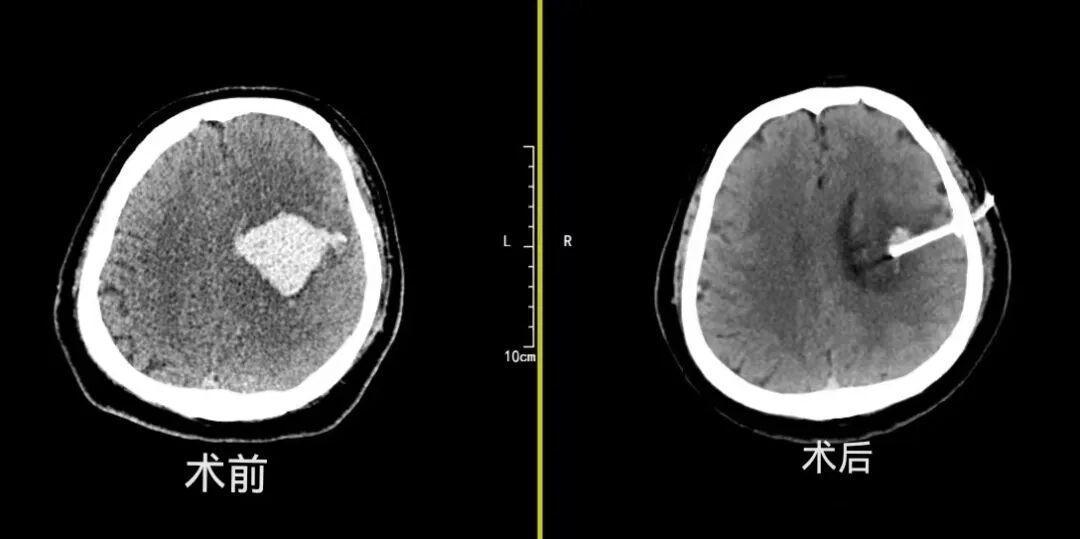

近日,40岁的脑出血患者王先生(假名)因出现相识朦拢被挫折送至病院,情况极度危险。靠近险情,神经外科副主任赵文礼团队断然为其推论CT雷同下可视穿刺抽诱骗流术。术后患者相识情状飞快改善,以两次尿激酶灌输休养,复查戒指显现其颅内血肿已基本拆除。最终,患者不仅奏效脱离了生命危险kaiyun体育,其神经功能也获取显赫规复kaiyun体育,康复远景考究。

脑出血病情不吉,传统开颅手术虽能拆除血肿,但创伤大、规复慢,好多乐龄、体弱患者难以耐受。而单纯的穿刺引流又存在“盲穿”风险,即使通过导航、立体定向等定位次序,由于无法直视下操作,穿刺时不敢抽吸过多,也不可详情残原谅况及是否有再出血情况,难以确保引流着力。CT雷同下可视穿刺抽诱骗流术奏效将脑出血穿刺手术,从传统的“警告脱手”升级至“影像导航、数据脱手”,其中枢上风在于“可视化”与“动态不雅察”,达成了术中“指哪打哪”的精确定位、“随时看清”的全程监测,从而达成对休养全进程的精确把控,显赫裁汰了再出血与穿刺副毁伤的风险,对基底节、丘脑等深部血肿的休养尤为适用。